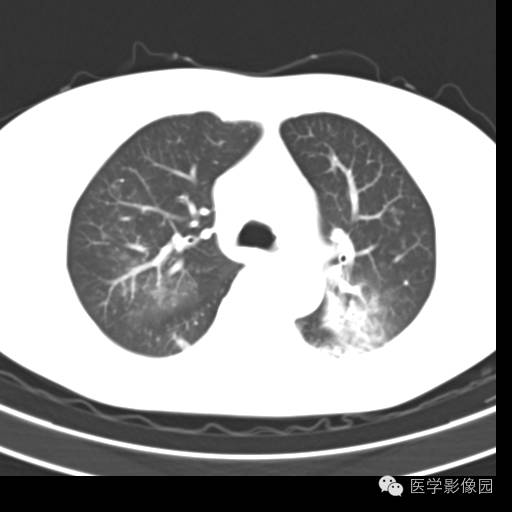

肺叶实变性支气管肺泡癌1例CT影像表现